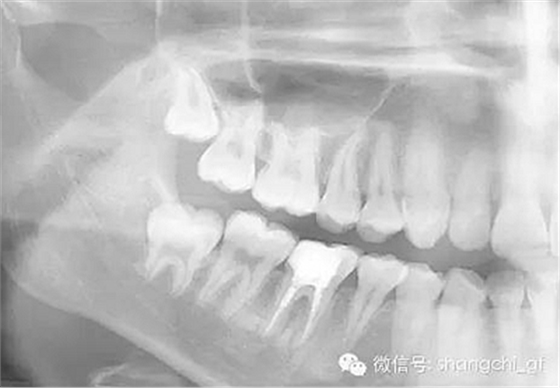

1.拍一張需要去除纖維樁的牙齒的X光片,仔細估算樁的長度,直徑。

手術(shù)前